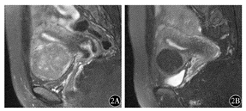

根据MRI信号特点将48个可评估肌瘤分组,行选择性UAE,本组病例均手术操作成功,未发生手术并发症,术后经抗感染及对症处理,患者恢复良好。术后分别于3、6、12个月行盆腔MRI扫描,测量肌瘤的体积大小(图1、图2)。UAE术后12个月,富于细胞性肌瘤体积缩小率高于普通未变性肌瘤和变性肌瘤,差异有统计学意义(P=0.038 ,P=0.014),而后二者之间差异无统计学意义(P=0.364)。体积≥35 cm3的肌瘤体积缩小率高于体积<35 cm3的肌瘤,差异有统计学意义(P=0.044)。黏膜下肌瘤的体积缩小率高于肌壁间肌瘤和浆膜下肌瘤(P=0.036 ,P=0.019 ),肌壁间肌瘤体积缩小率高于浆膜下肌瘤,但差异无统计学意义(P=0.384)(表1)。UAE术后肌瘤体积缩小以3个月内明显,尤其是富于细胞性肌瘤、黏膜下肌瘤体积缩小明显,达到70%左右,以后逐渐变慢,6个月以后体积缩小缓慢。黏膜下肌瘤可自行脱落,或在医生帮助下钳夹脱落,达到治愈目的。

1A:介入治疗前,1号肌瘤呈类圆形低信号肿块影,边界清楚,周围环绕高信号,大小3.0 cm×4.2 cm×3.6 cm; 2号为后壁肌壁间肌瘤,部分凸入黏膜下,宫腔受压变形;1B:介入治疗后12个月,1号肌瘤呈极低信号,体积缩小率为51.8 %;2号肌瘤信号增高,与肌层信号接近,考虑肌瘤水肿所致,体积无明显变化